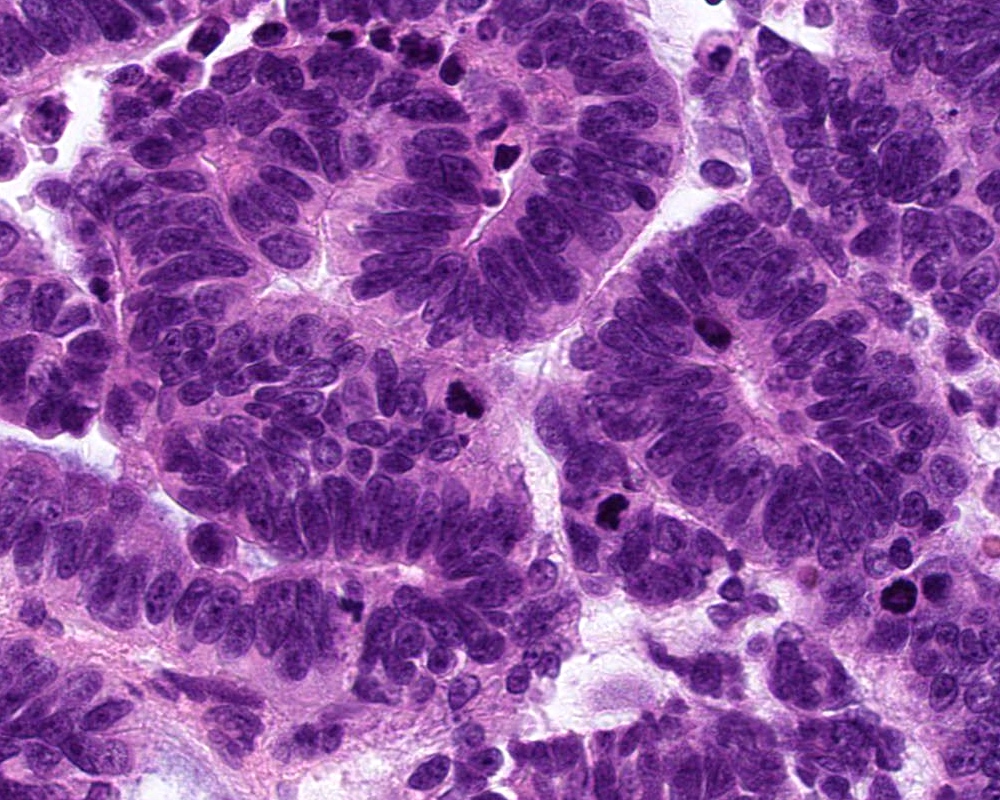

Microscopic (histologic) description

- Atypical choroid plexus papilloma (aCPP, WHO grade 2):

- Higher cellularity relative to CPP

- Moderate nuclear pleomorphism, blurring of papillary pattern

- Occasional mitoses (> 2/10 high power fields), with or without necrosis

- Choroid plexus carcinoma (CPC, WHO grade 3):

- Frankly malignant

- High cellularity, hyperchromatic nuclei and nuclear pleomorphism

- Blurring of papillary pattern and solid arrangement

- Frequent mitoses (> 5/10 high power fields), necrosis, with or without brain invasion

Microscopic (histologic) images

B. Recent studies suggest 3 distinct molecular entities based on methylation profiling, patient age and tumor location. An atypical choroid plexus tumor is shown in the image.